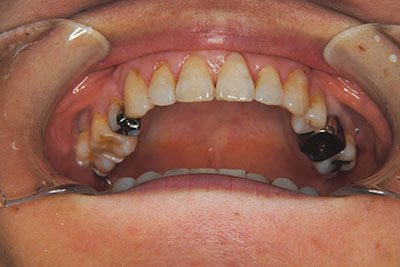

子供の頃に矯正治療を行う方が治療期間が短く済むというのは、確かですが、矯正治療は患者様の意識も重要です。

いくら歯が動き易くとも、本人がやる気でなければ効果は出ませんし、むし歯発生のリスクも高まります。おとなの方は顎の成長が終わっているため、治療の計画が立てやすいとも言えます。「もう大人だから…」とあきらめず、一度ご相談ください。